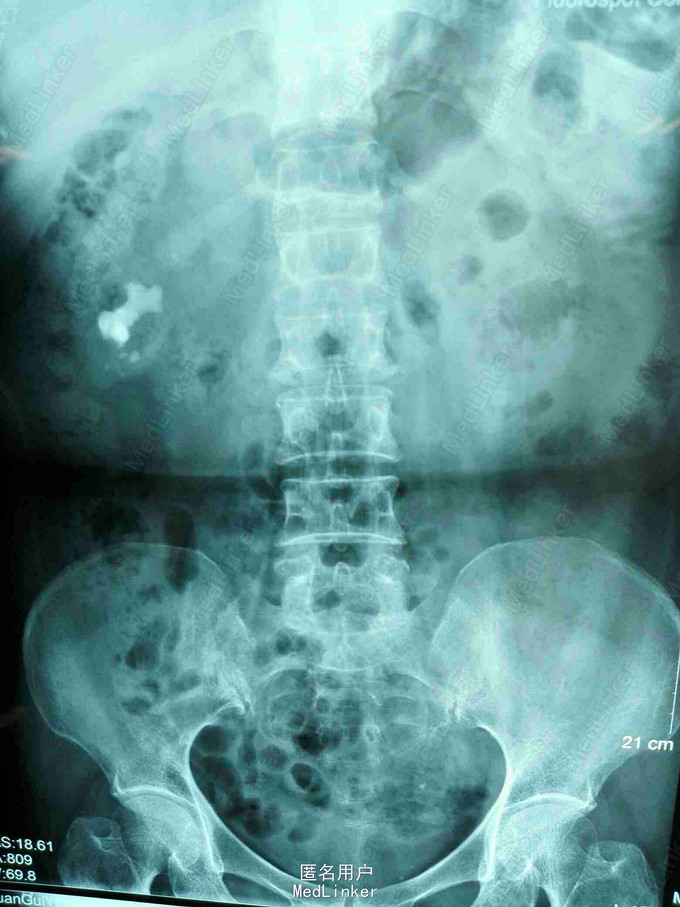

发现右肾结石10余年入院。无腰痛,无尿频、尿急、尿痛,无脓尿,无肉眼血尿。曾行体外碎石不次(具体不详),有反复尿路感染病史。

术前诊断:右肾结石并积液。 因患者血型特殊,患者要求行软镜碎石,经讨论后还有是行PCNL术。 取11肋下腋后线交点穿刺,X线定位,穿入中下盏,见称薄脓液流出,扩张至F18,F12李逊肾镜,结石边碎边吸,见术中无特殊不适,一期完成PCNl术。手术时间35分钟,出血少量。 术后诊断:右肾结石并积脓